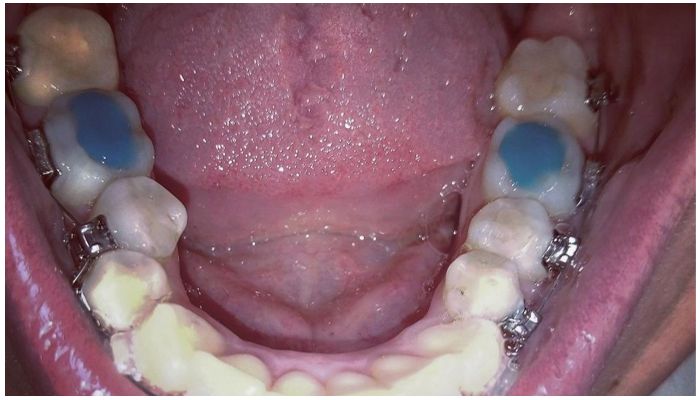

Временные защитные конструкции делают из разных материалов:

• Искусственный дентин. Берется композитный порошок и разводится водой в нужной пропорции. Полученная субстанция накладывается на жевательную часть и затвердевает за 2 часа.

• Дентин-паста. Композитная порошкообразная масса смешивается с антисептическими маслянистыми веществами. После нанесения самостоятельно застывает на поверхности зуба.

• Цемент. Прочный материал, использование которого показано при бруксизме, плохом качестве зубов.

• Полимер. Данный материал напоминает мягкую резиновую массу. Она наносится на поверхность моляра или брекета и просвечивается лампой. Надкусочная пломба застывает в течение нескольких минут.